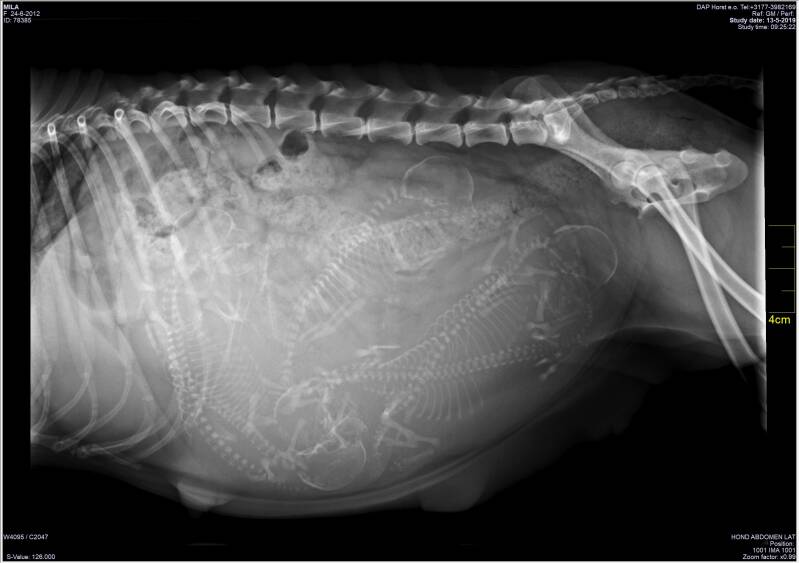

Röntgenfoto Mila

Vandaag was het zover... op de vraag hoeveel pups er in Mila's buikje zitten komt vandaag antwoord.

Het is lastig te tellen maar als je goed kijkt zie je 6 pups zitten. De dierenarts verwacht de pups eind deze week. Nu hopen op een goede bevalling!